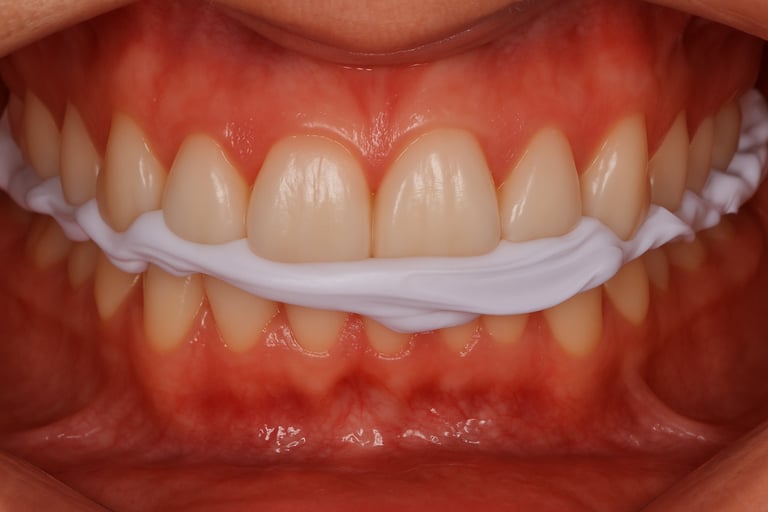

O DVR-Sensy foi desenvolvido para superar essas limitações por meio de uma abordagem sensório-fisiológica controlada.

Embora seja um dispositivo posicionado entre as arcadas, sua função é substancialmente distinta dos métodos interoclusais convencionais.

O DVR-Sensy atua como um estabilizador de fechamento mandibular, e não como um espaçador.

Sua geometria apresenta altura progressiva — mais baixa na região posterior e gradualmente elevada na anterior — e estrutura deformável que permite microdeslizamentos sem bloqueio muscular.

O material de baixa resistência possibilita a continuidade da propriocepção durante o fechamento, de modo que o movimento mandibular não é interrompido, mas guiado fisiologicamente até que ocorra o silêncio neuromuscular — o ponto em que a atividade dos músculos elevadores atinge estabilidade e cessação funcional.

A principal diferença entre o DVR-Sensy e os dispositivos convencionais está na forma como o sistema neuromuscular é envolvido no processo de registro.

Enquanto os métodos tradicionais impõem uma posição, o DVR-Sensy permite que o próprio sistema determine sua posição de repouso.

Durante o fechamento com o DVR-Sensy, o paciente realiza um movimento natural e não forçado.

Esse movimento é interpretado pelo sistema sensorial periodontal e muscular, que ajusta o tônus e busca espontaneamente o equilíbrio fisiológico.

Quando a musculatura atinge o silêncio neuromuscular, a mandíbula estabiliza-se tridimensionalmente — e essa posição é registrada de forma direta e física.

Assim, o DVR-Sensy não mede uma uma distância linear; ele registra a relação espacial tridimensional entre as arcadas no momento de repouso fisiológico.

Na prática clínica, o uso do DVR-Sensy resulta em dispositivos com alto grau de compatibilidade fisiológica e menor necessidade de retrabalho clínico.

O equilíbrio oclusal obtido tende a ser mais previsível, pois deriva de uma posição mandibular não induzida.

Essa previsibilidade se traduz em melhor adaptação inicial, menor necessidade de ajustes corretivos e maior estabilidade funcional no uso prolongado.